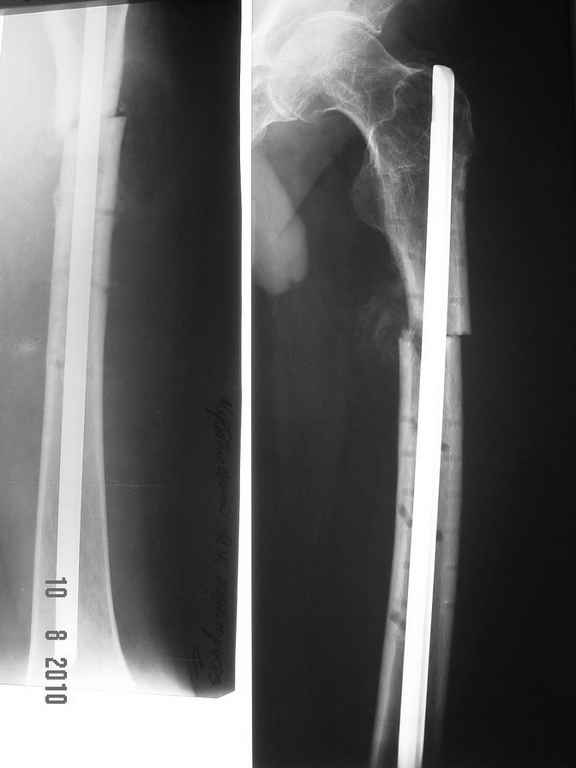

ДОбавил фото....

Условия больницы не блещут как собственно и финансовые возможности больного. Варианты типа БИОС, бусы с антибиотиками наверное так и останутся "вариантами". Пока интересует вопрос - остеомиелит? что делать?

Здесь, мне кажется, не только осложнение послеоперационной раны, а также имеется технические погрешности установки гвоздя. Трохантерная точка введения гвоздя является идеальной для антеградных гвоздей, но такие гвозди имеют изгиб в 4-5 градусов. Повело в варус за счет трансляции на диафизе, а также имеется подозрение на ротацию.

При желании, любой интрамедуллярный гвоздь с помощи пары шурупов в гвоздь или мимо гвоздя можно превратить в блокирующую конструкцию. Более стабильная конструкция дает лучше возможности ранней активности и нагрузки.

Поперечные переломы более стабильные в нагрузке, и учитывая, что с момента операции прошло не менее трех недель, сейчас можно разрешить полную нагрузку.